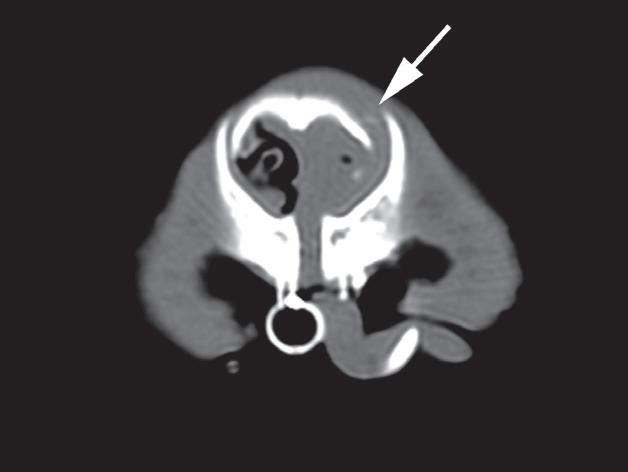

Badanie wykonano u 5-letniego, kastrowanego kota rasy europejskiej po urazie o nieznanej przyczynie, do którego doszło w ciągu 48 godzin poprzedzających badanie. U kota stwierdzono liczne złamania czaszki typowe dla urazów o dużej sile. Prezentowane obrazy ułożono w kolejności od donosowej do doogonowej. Urazy obejmują: złamanie lub zwichnięcie w obrębie kości nosowych i szczękowych (a – strzałka), separacje spojenia żuchwy (b – strzałka), złamania wyrostków pionowych kości podniebiennych (c – strzałki), rozejście spojenia podniebiennego (c – grot strzałki), złamania kości skrzydłowych (d – strzałki), doogonowe zwichnięcie prawego wyrostka kłykciowego (e – grot strzałki) oraz złamanie przez wyrostek jarzmowy lewej kości skroniowej (e – strzałka)